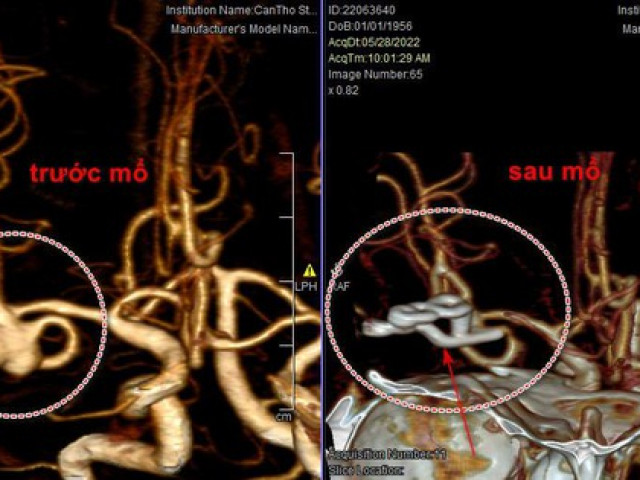

Tắc nghẽn mạch máu rất nguy hiểm, nó có thể gây ra nhồi máu cơ tim, nhồi máu não và nhiều bệnh lý nghiêm trọng khác. Vì vậy, khi phát hiện ra các dấu hiệu của tắc nghẽn mạch máu, bạn cần được cấp cứu kịp thời để tránh nguy hiểm tới tính mạng.